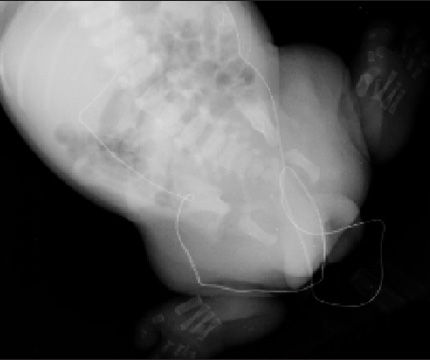

A baby boy born at 37 weeks’ gestation via cesarean delivery for breech presentation

was noted to have marked malformation of the bilateral lower extremities with absent

proximal and distal segments, and left hallux conjoined with the second toe. Radiographs showed absence of the acetabulum, femur, tibia, fibula, and tarsal bones bilaterally. These findings were consistent with caudal regression syndrome.